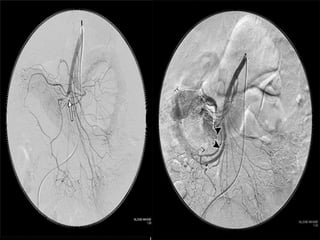

Angiography

It is the gold standard for

diagnosis of mesenteric vascular

occlusion.

63-year-old woman status post aortic valve replacement who presents with a one

week history of abdominal pain becoming quite severe over the last 24 hours.

Post OP - Diffuse vasospasm

without occlusions.

Post Papaverine infusion

Arteriogram 24 hr later.

Reversal of vasospasm.